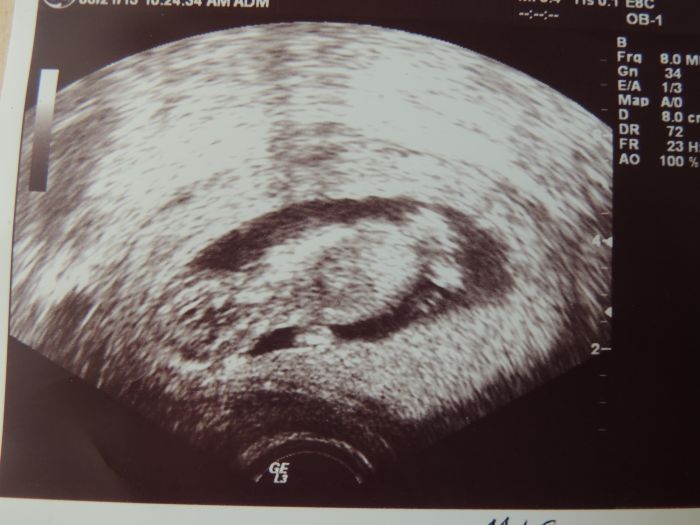

Taky jsem v pátek měla trochu paniku. Bolesti břícha. Doktorka mě pak chtěla vidět a tak jsem jela do Prahy, prcek vrtěl, mrskal ručičkama a nožičkama, až jsem se tam nekontrolovaně rozbulela a omlouvala se

. Hormony nebo co ??

. Prý to byla asi nějaká střevní záležitost ( měla jsem i průjem, což nemívám, spíš naopak) Tak jsem si říkala, jestli nejsem trochu histerická

. Doktorka je ale v pohodě, takže mi dala obrázek, pohladila po břichu a já jela šťastně domů...